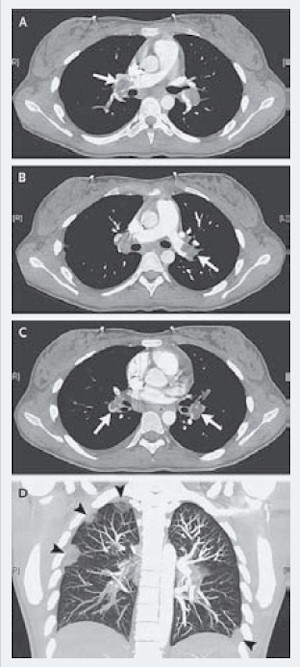

Компьютерная томография грудной клетки подтвердила наличие крупных тромбов в просвете правой и левой легочных артерий (рис. 1А и 1В), а также сегментарных легочных артерий с обеих сторон (рис. 1С). При трехмерном воссоздании структуры легких во фронтальной плоскости в обоих легких определялись множественные периферические участки затемнения (инфаркты ткани легкого), а также небольшой двусторонний плевральный выпот (рис. 1D).

Рисунок 1. Результаты компьютерной ангиографии: стрелками указаны тромбы в просвете правой легочной артерии (1А), левой легочной артерии (1В), сегментарных легочных артериях с обеих сторон (1С).

На рисунке 1D представлены результаты трехмерного воссоздания структуры легких во фронтальной плоскости (стрелками указаны инфаркты легкого и плевральный выпот).

Первые сутки пребывания в клинике (исследование выполнено сразу после госпитализации).

Рисунок размещен с любезного разрешения редакции New England Journal of Medicine.